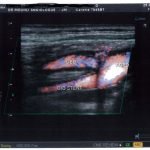

Accueil stenting carotide interne droite et plaque anfractueuse et stenosante sur la Carotide primitive droite non visualisé par l’angioscanner et l’angiographie stenting carotide interne droite et plaque anfractueuse et stenosante sur la Carotide primitive droite non visualisé par l'angioscanner et l'angiographie